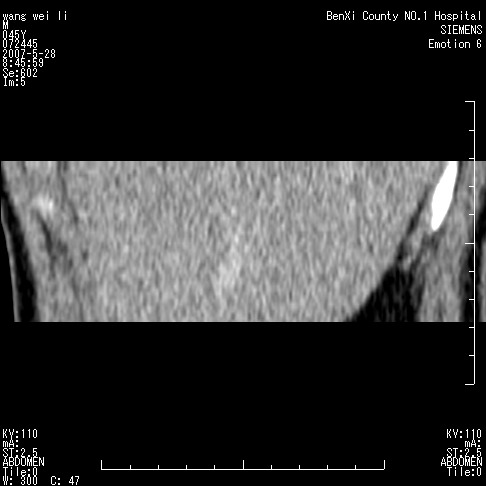

以下是引用还珠格格在2007-5-28 12:06:00的发言:[br]肝右叶后段病灶动脉期结节状强化,既然静脉期、延迟期为等密度充填 应考虑 肝右叶后段典型血管瘤。